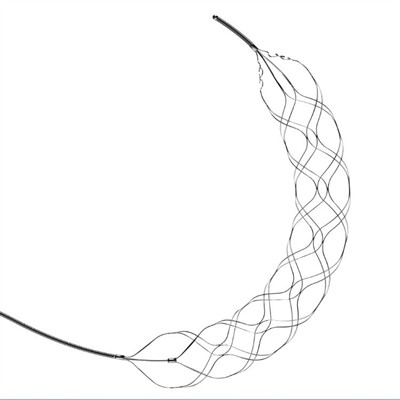

Преимущества ретривера стента для тромбэктомииВ последние годы тромбэктомические стент-ретриверы стали высокоэффективным вариантом лечения пациентов, перенесших острый ишемический инсульт. Эта минимально инвазивная процедура включает в себя введе

Типы устройств для тромбэктомииИнсульт является основной причиной инвалидности и смертности во всем мире. В последние годы разработка устройств для тромбэктомии для лечения острого ишемического инсульта произвела революцию в медици